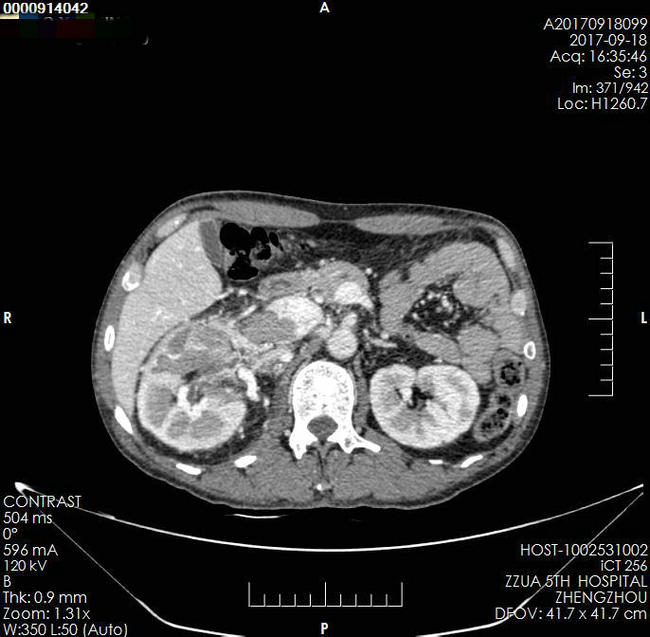

▲ 术前SCT、超声影像检查结果

患者,男,49岁,发现腹腔巨大占位1月余入院。平素患者无特殊不适,既往史、家族史无特殊。近1月来消瘦,曾辗转就诊省内三家三级医院,建议放弃手术。入院诊断:右肾巨大肿瘤并下腔静脉癌栓Mayo Ⅲ级(癌栓远端达第二肝门水平)。

▲ 术前影像资料